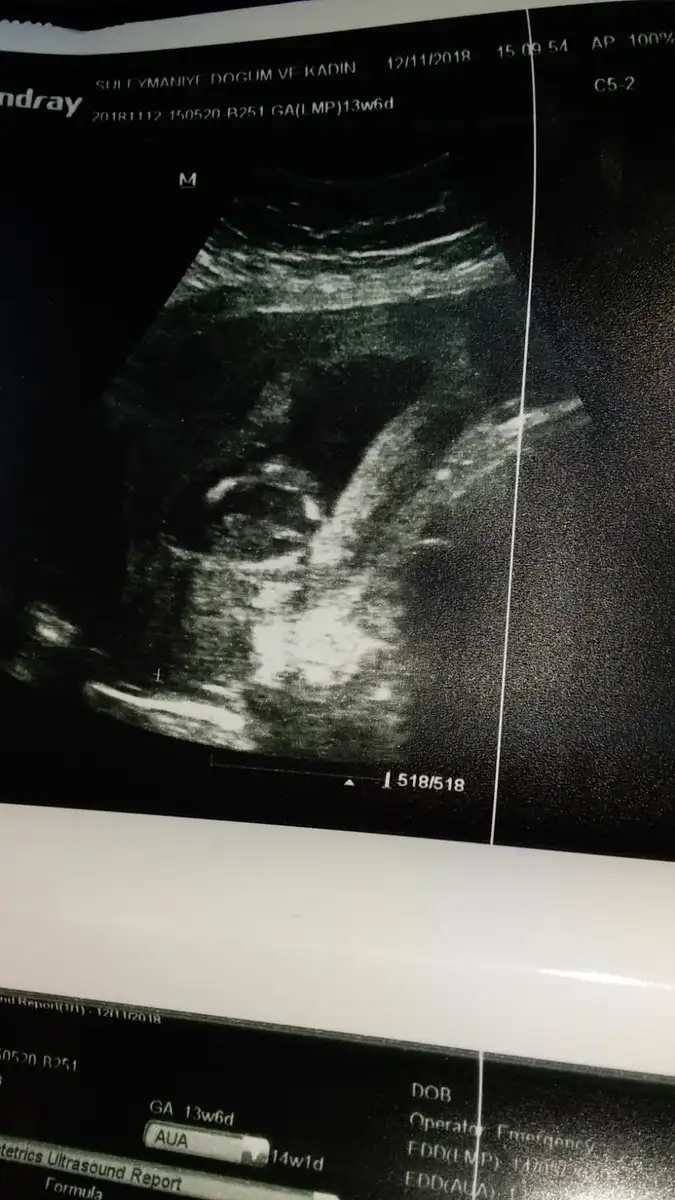

Hanimlar 13+6 dr um cinsiyet belli değil dedi kızlar belli etmez kız mı diye sordum öyle bir şey diyemem dedi bacak arası açık gibi tahmini olan var mi

Kiz gibi kesenin solunda erkek saginda kizEki Görüntüle 2216898